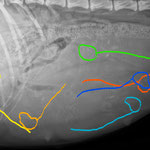

Hündinnen tragen normalerweise 63 Tage. Da man aber (ohne aufwändige medizinische Tests) den genauen Zeitpunkt des Eisprungs nur nach dem Datum der Deckungsbereitschaft der Hündin abschätzen kann, bleibt auch der voraussichtliche Wurftermin nur eine Schätzung. Erst ab dem 25. Trächtigkeitstag kann man mittels Ultraschall feststellen, ob die Hündin überhaupt trägt. Ihr äusserlich ansehen kann man das sogar erst ab ungefähr dem 40. Tag. Es könnte ja aber auch immer noch eine Scheinträchtigkeit sein. Gewissheit gibt ein Röntgen, das ab dem 45. Tag gefahrlos gemacht werden kann.